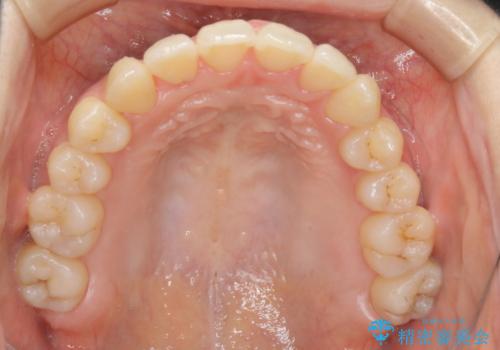

本来は外科ケース:インビザラインで前歯の重度がたつきとオープンバイトの改善

元々の骨格的なズレが大きかったため、当初は外科矯正をご提案していました。患者様の強いご希望により、非外科的な処置のみで可及的な改善を目指すことを目標に治療を行いました。以前よりもしっかり噛めるようになり、見た目も劇的に改善したことで大変ご満足いただけました。